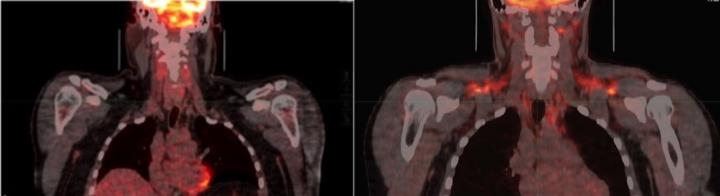

image: People have a few grams of brown fat that is activated when the body is cold. Brown fat uses sugar, fat and amino acids from the blood to generate heat. Left: Brown fat is not activated. Right: Cold conditions activate the brown fat as shown by the orange color on both shoulders and the neck.

Brown fat is considered a heat organ. People have a few grams of it in areas including the neck, collarbone, kidneys and spinal cord. When activated by cool temperatures, brown fat uses sugar and fat from the blood to generate heat in the body.